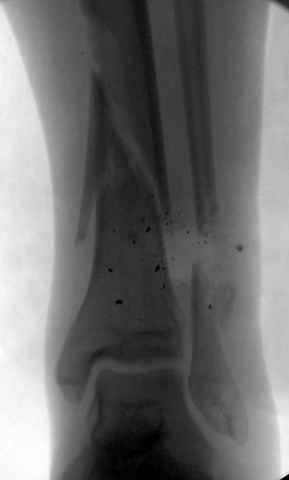

На снимках варианты фиксации малоберцовой:

№ 1 двух лодыжек